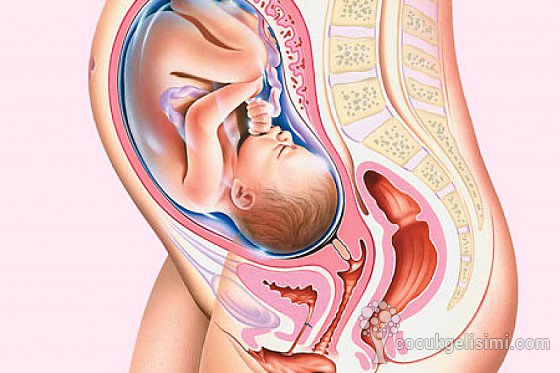

Развитие плода на 31 неделе беременности